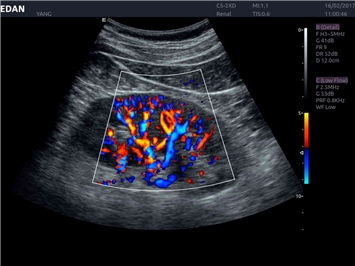

EDAN Acclarix LX4

Расширьте свои представления. Использование усовершенствованной платформой Acclarix система LX4 обеспечивает непревзойденную четкость изображений и интеллектуальный рабочий процесс для всех пользователей, являясь при этом наиболее экономичным решением.

EDAN Acclarix LX4 представляет собой инновационную ультразвуковую систему, построенную на усовершенствованной платформе Acclarix. Сочетание высокого качества визуализации с интеллектуальным рабочим процессом делает эту систему оптимальным выбором для клиник, ценящих эффективность и экономичность.

Трехмерная реконструкция ЦДК:

Да

Энергетический допплер:

Цветовой допплер: